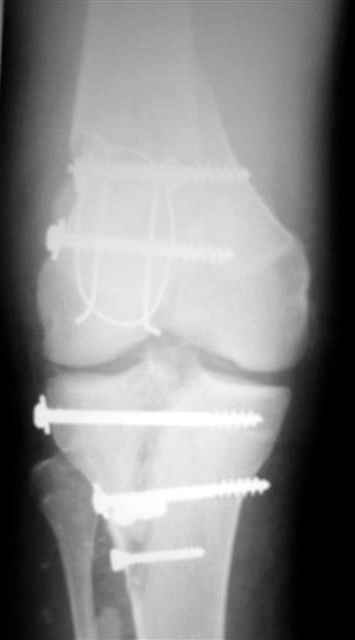

Вид раны на сегодня...

4 cутки после травмы.

Спасибо за комментарии. Травма тяжелая с проблематичным прогнозом для функции коленного сустава( изначально травма разгибательного аппарата с последующим частичным некрозом собственной связки надколенника и о обнажением рефиксированного фрагмента бугристости большеберцовой кости, дефектом центрального отдела суставной поверхности большеберцовой кости и медиального отдела капсулы сустава).